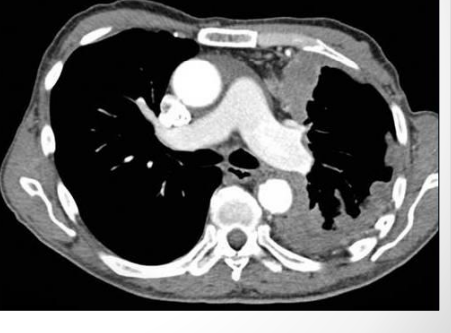

3

Q

This image shows a chest CT of the lungs. What pathology is depicted? [1]

A

Pleural effusion

Lung border is white bit